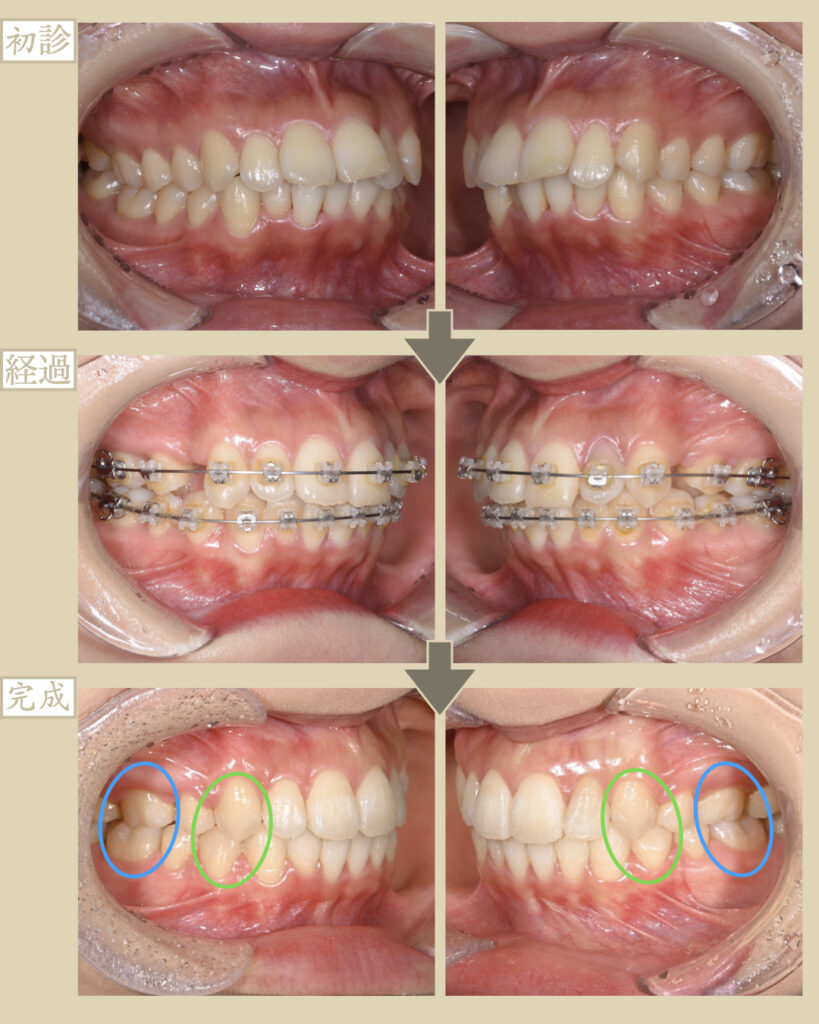

- 主訴:前歯が出ているのが気になる

- 抜歯:あり

- 装置:表側ワイヤー矯正

- 期間:2年半

- 費用:100万円(税別)+調整量月5,000円

① 奥歯から動揺や破折しやすい

出っ歯のため前歯で噛めないので、奥歯のみで力の負担を支えている状態です。

そのため、将来的に奥歯からグラグラしてきたり破折しやすいことが問題として考えられます。

上顎左右4番目の歯を抜歯して、歯の移動スペースを確保する。

ワイヤー矯正は、前歯群と奥歯群の引っ張り合いで綺麗なアーチ状にしていきますが…

今回は、出っ歯の症例のため、奥歯群が前に引っ張られないようにゴム掛けを工夫してなるべく前歯だけを後退。

これにより、抜歯した4番目のスペースを活用して、奥歯群は前に移動させずに前歯群だけを後ろへと移動させて、大幅に出っ歯を改善させていきます。

問題点のかみあわせも全体で噛めるようになり、歯の健康寿命が増進しました。

また、出っ歯の改善による虫歯や歯周病のリスクを軽減させ、

口元が引っ込んだ事Eラインができ、相乗的に鼻が高く見えて顎先も出ることで、凹凸のある美しい横顔になりました。

また、梅干しあごの改善と唇を自然に閉じることができました。